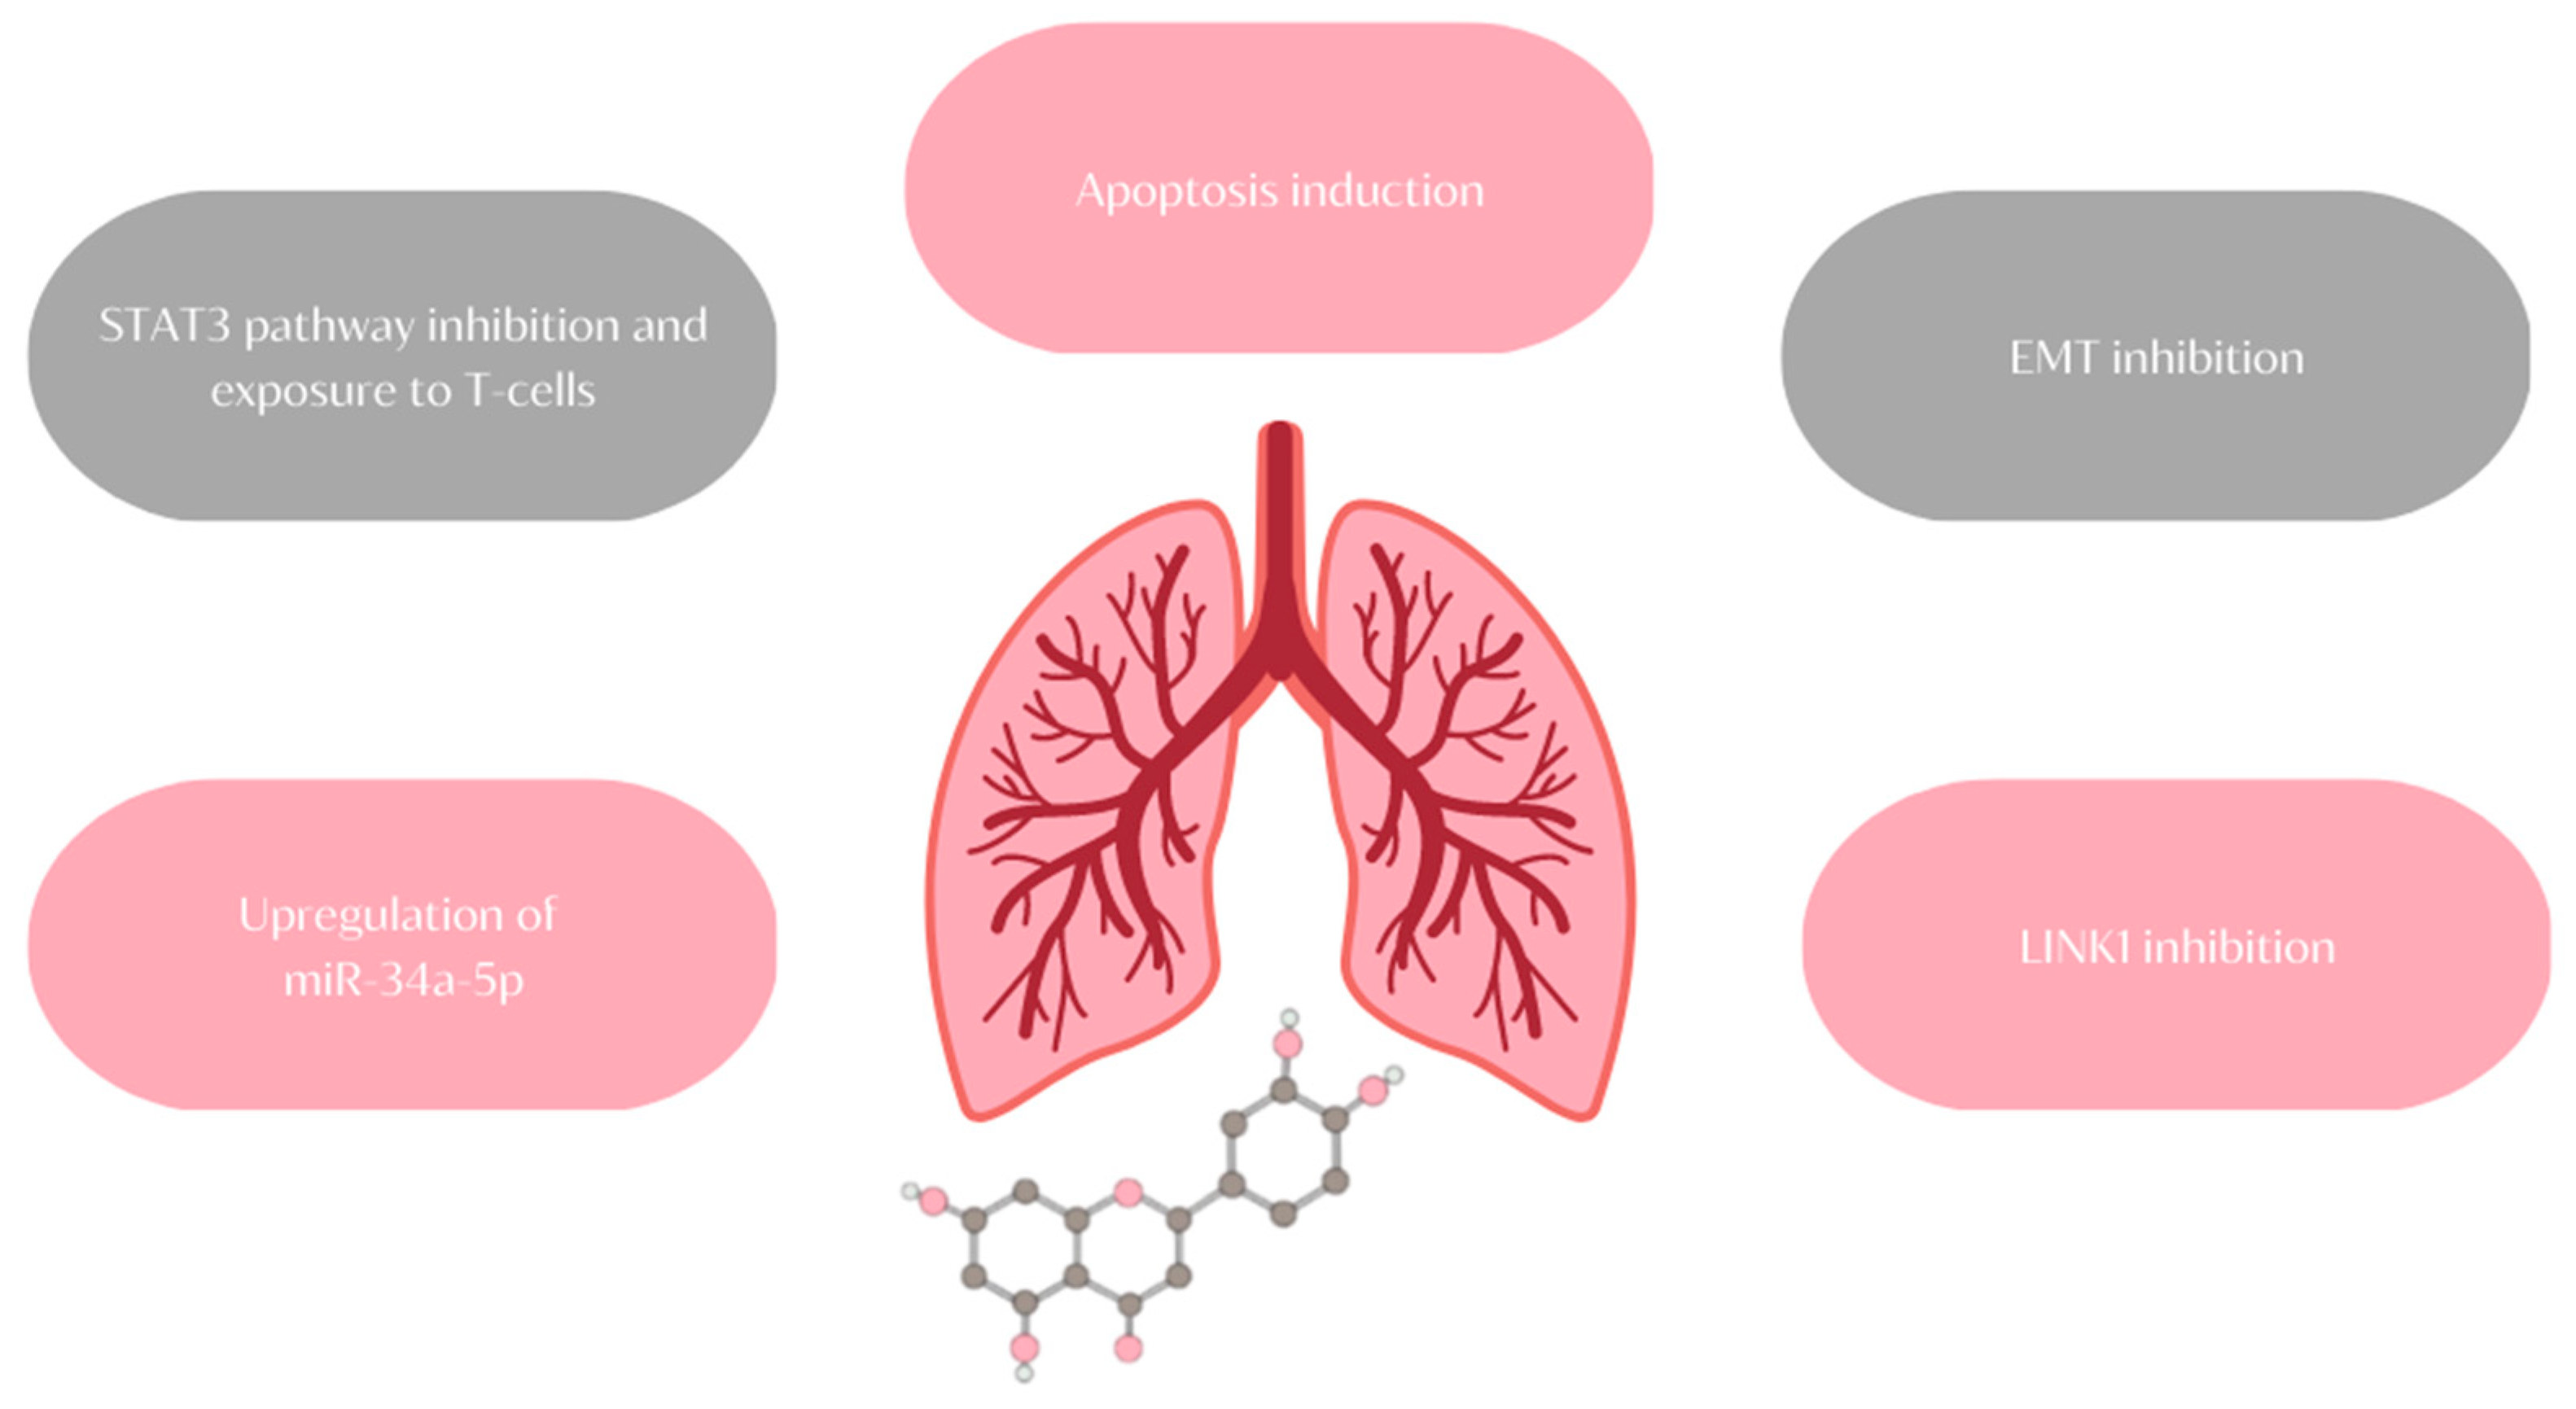

- Suppress the growth of triple-negative/basal-like ERα-negative MDA-MB-231 cells;

11. Lung Cancer